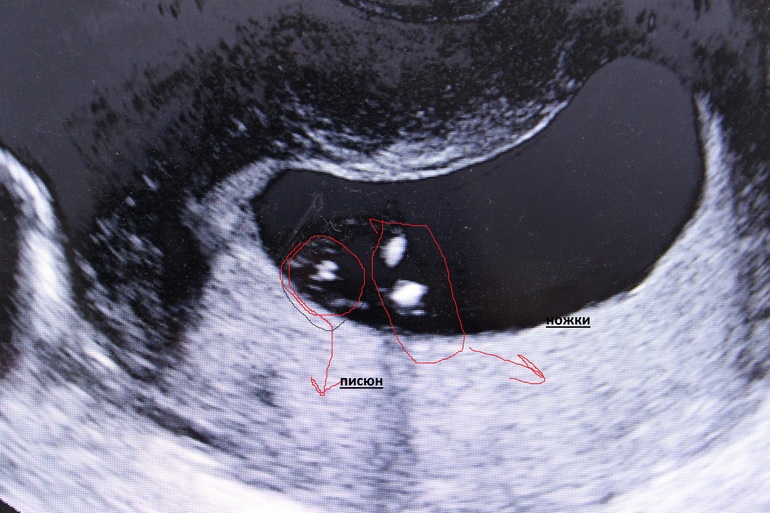

Вопросы про УЗИ, обследования и анализы: что, где, как, когда?получила диск - сделала с него фото

все глаза сломала по мне так не понятен пол

а вы как думаете?

фото под кат - вид сидящего малыша - т.е фото снизу как бы

у нас угол как раз и сложно было глянуть так как он лежал как хотел но не на боку. меня узистка даже кашлять заставила чтобы на бок лег замеры сделать. а когда лег взял и прикрыл свое добро ножками)))